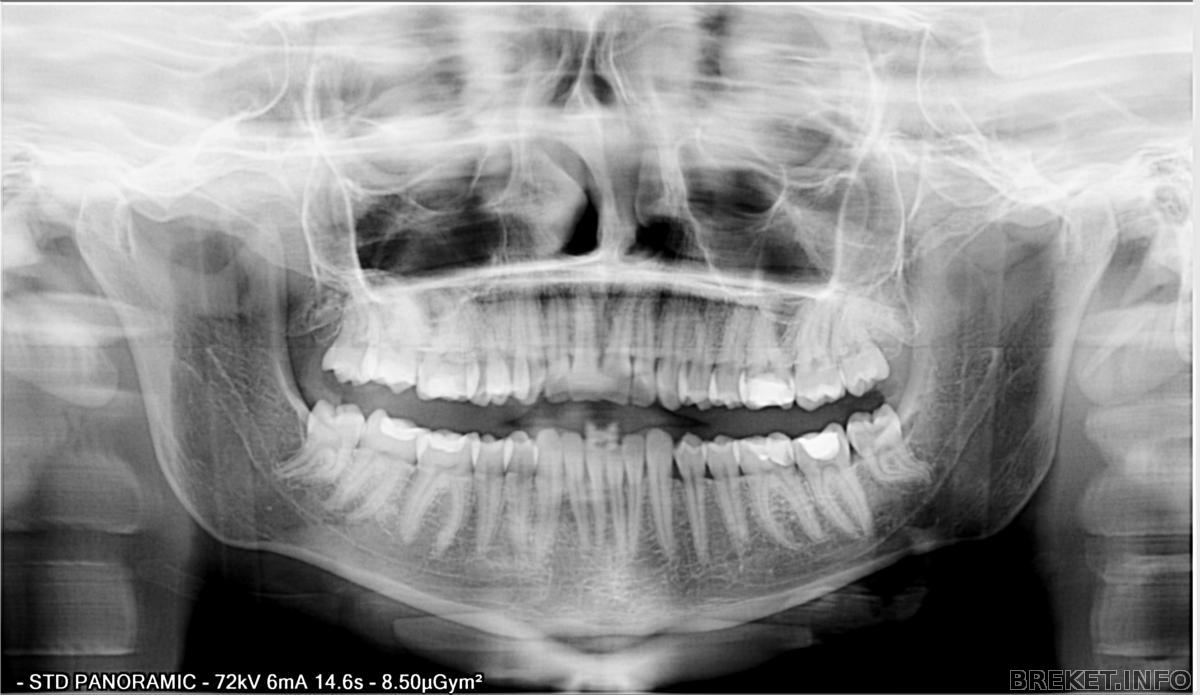

Mrs. El, оооо, да, всё верно, под углом, посмотрела ОПТГ - под углом корень, надо ему этот снимок на лоб приклеить, что б увидел.

И вот снимок кстати, это до лечения, ну я не думаю, что положение корня уж очень поменялось, наклон тот же